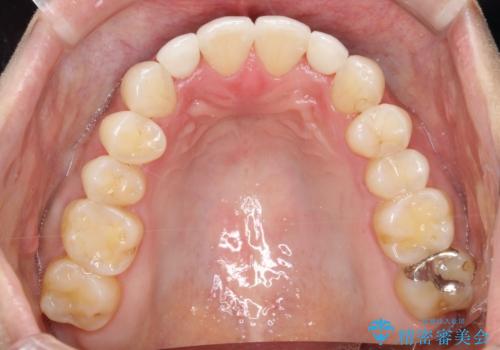

【インビザライン】矮小歯を有する方の矯正治療

- 前歯の凸凹を主訴に来院されました。

元々、歯が小さかったため矯正終了後にセラミックにて修復治療を行う治療計画をたてインビザラインにて治療を行いました。

今回はスペースを作るために歯列の拡大をメインでおこなっています。